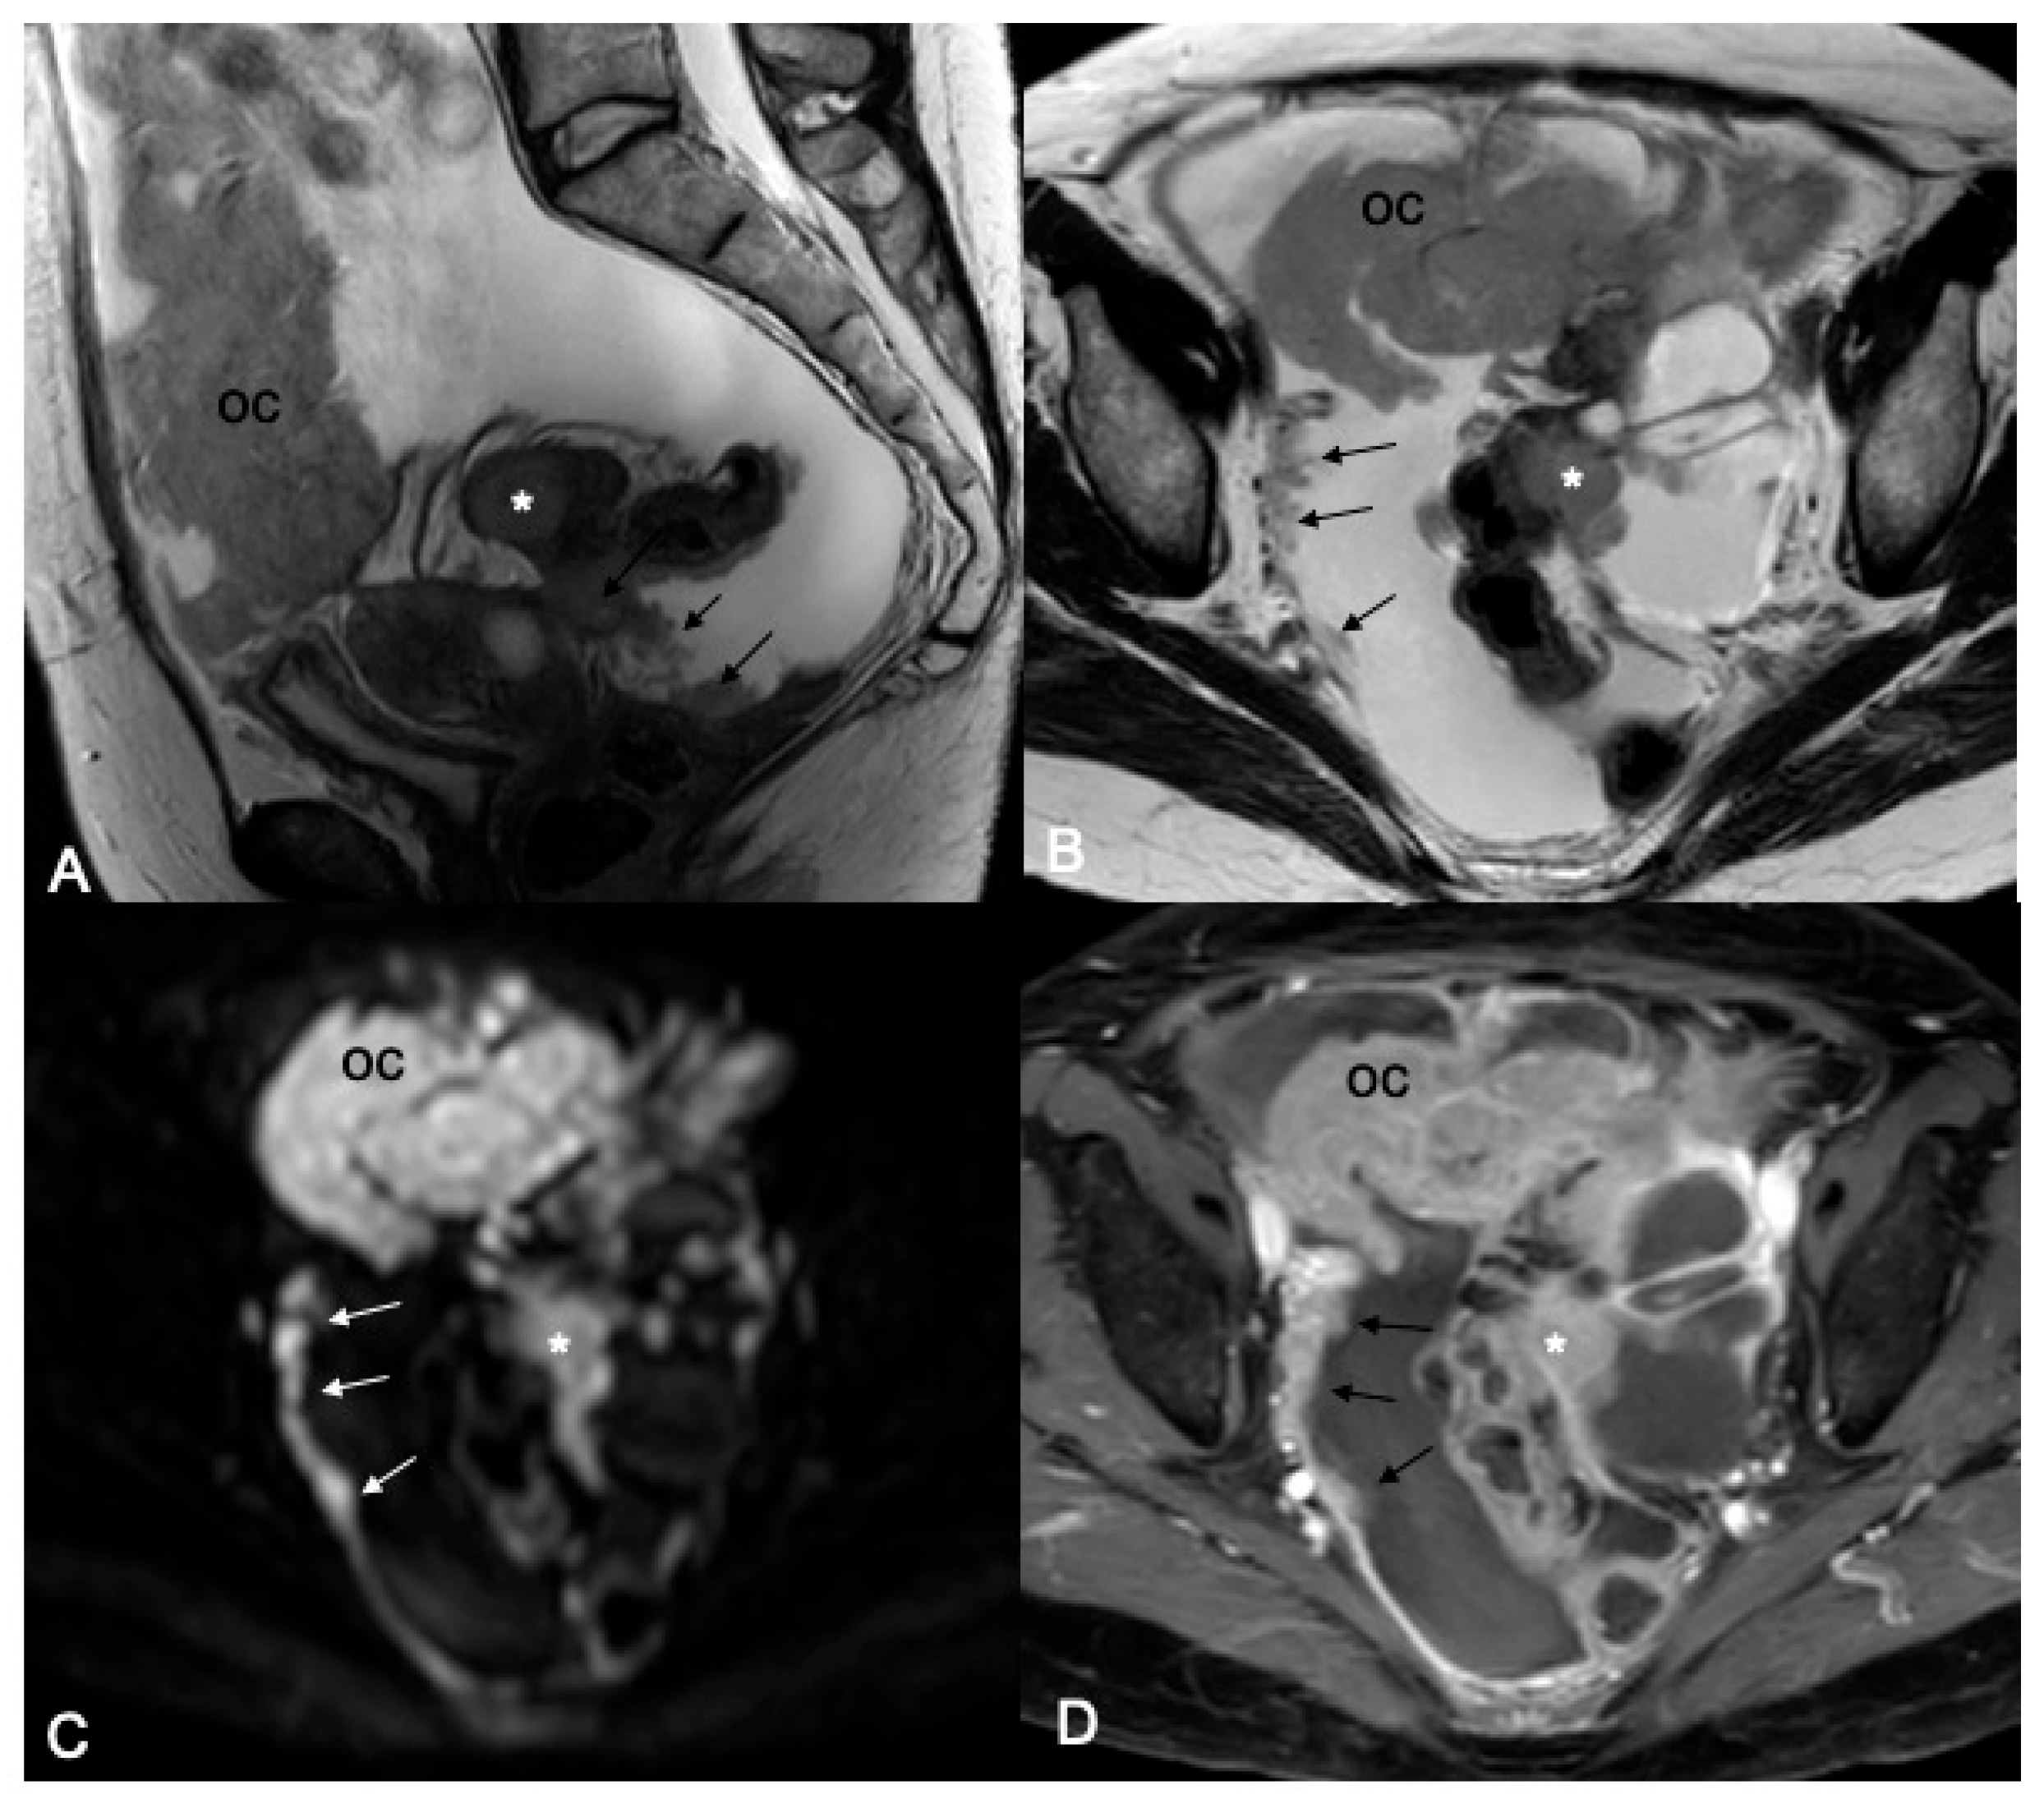

Background/Objectives: Cytoreduction status is a critical prognostic factor in ovarian cancer, yet preoperative selection of patients suitable for primary debulking surgery and accurate prediction of surgical outcome remain challenging. This study aimed to evaluate the prognostic ability of MRI-based Fagotti score and Peritoneal Cancer Index (PCI) for predicting resectability of peritoneal disease in ovarian cancer patients. Methods: This was a prospective single-center observational study. Patients with suspected primary ovarian cancer who underwent preoperative MRI of the abdomen and pelvis with a dedicated protocol were considered. MRI-based Fagotti score and PCI were determined by two readers independently, using a combination of T2W, Diffusion-Weighted Imaging (DWI), and contrast-enhanced T1W sequences. In cases of discordance, a third radiologist reviewed the scans and consensus was reached. ROC analysis and logistic regression were used to evaluate prognostic performance. The reference standard to predict resectability was optimal cytoreduction defined as residual disease ≤1 cm. Results: Forty-six women with epithelial ovarian cancer (mean age 56.3 ± 2.6 years) who underwent preoperative MRI, followed by laparoscopy and/or laparotomy, were included in the study. Both MRI-based Fagotti score and PCI showed high predictive value for predicting resectability (AUC 0.92 and 0.94, respectively). Optimal cut-offs were ≤6 for Fagotti score and ≤20 for PCI. Patients with scores below these thresholds had >60-fold (Fagotti) and >100-fold (PCI) increased odds for successful primary cytoreduction (p < 0.001). Conclusions: MRI-based Fagotti score and PCI may serve as powerful noninvasive predictors of surgical outcome in ovarian cancer. MRI may reliably guide treatment decisions, reducing unnecessary laparotomies and optimizing patient selection.